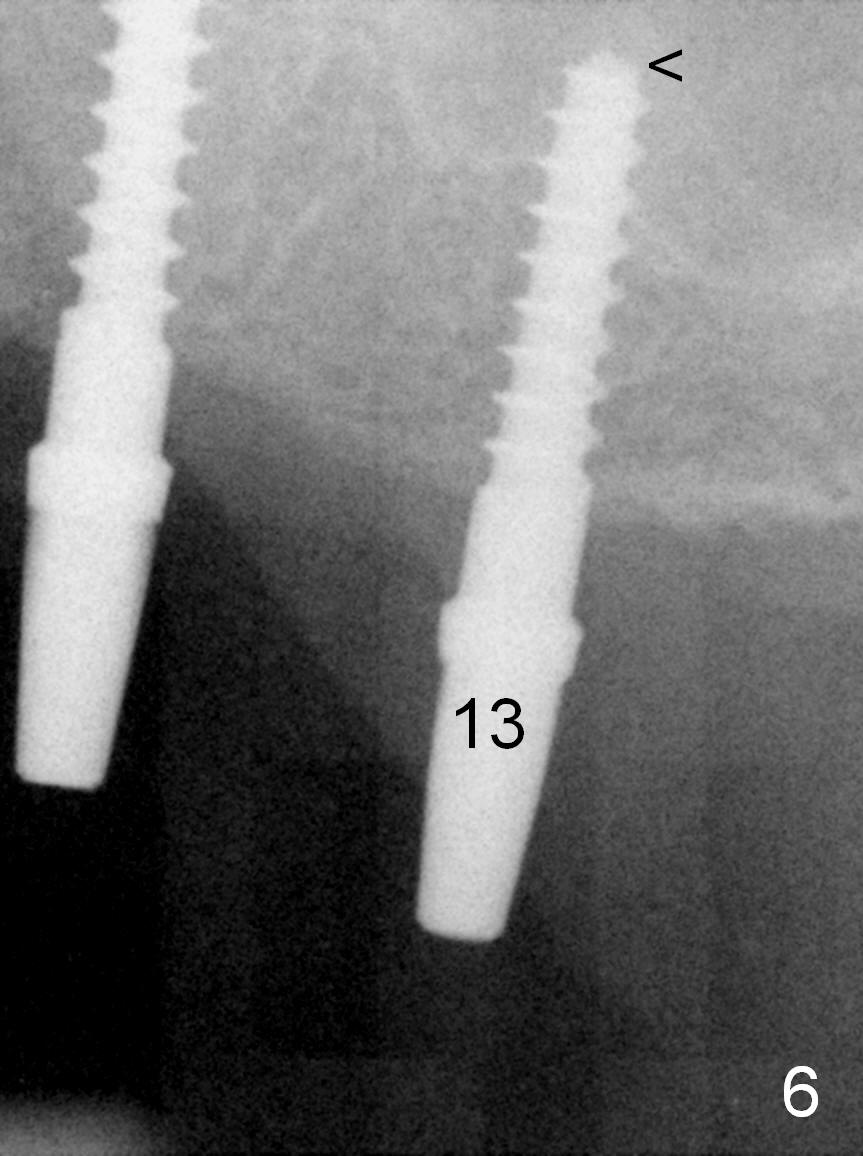

When the patient returns for implant placement (2nd visit after initial exam), he reveals that he is a dental phobic. He requests placement of 4 implants in the upper left quadrant, instead of 2. Narrow ridge is unexpected in the canine and premolar area (Fig.1). Limited bone height at #13 (Fig.3 arrowheads: sinus floor) is found when initial drills are in place (Fig.2,3). A 2-piece implant (4.5x17 mm tissue-level) is placed at #10 after extraction, while 1-piece implants are placed at 11 (3x17 mm (tissue-level, 15 °) and 12 and 13 (bone-level, 2.5x14, 12 mm, respectively; Fig.4,5). In fact the 1 piece implant at #13 is not completely placed (Fig.5). It is removed, the apical 3 threads are cut off (Fig.6 <, since a shorter implant was unavailable in the office) and the remaining implant is re-inserted. The insertion torques of the 4 implants are ~ 60, ~ 35, < 35 and 15 Ncm, respectively. After adjustment (Fig.7), immediate provisionals are fabricated at #10 and 11 (Fig.8, later splinted with composite), while perio dressing is applied around the implants at #12 and 13 and the provisionals at #10 and 11. There is no nasal hemorrhage postop. Although the perio dressing is loose 1 week postop (Fig.9), it is not removed. When the upper lip fissure (Fig.9 <) heals, provisionals at #12 and 13 are planned to be splinted to the other two ones. Two weeks postop, the upper lip fissure heals, the perio dressing dislodges and the implants at #12 and 13 are stable (Fig.10). After abutment height adjustment, a splinted provisional is fabricated over these 2.5 mm 1-piece implants (Fig.11).